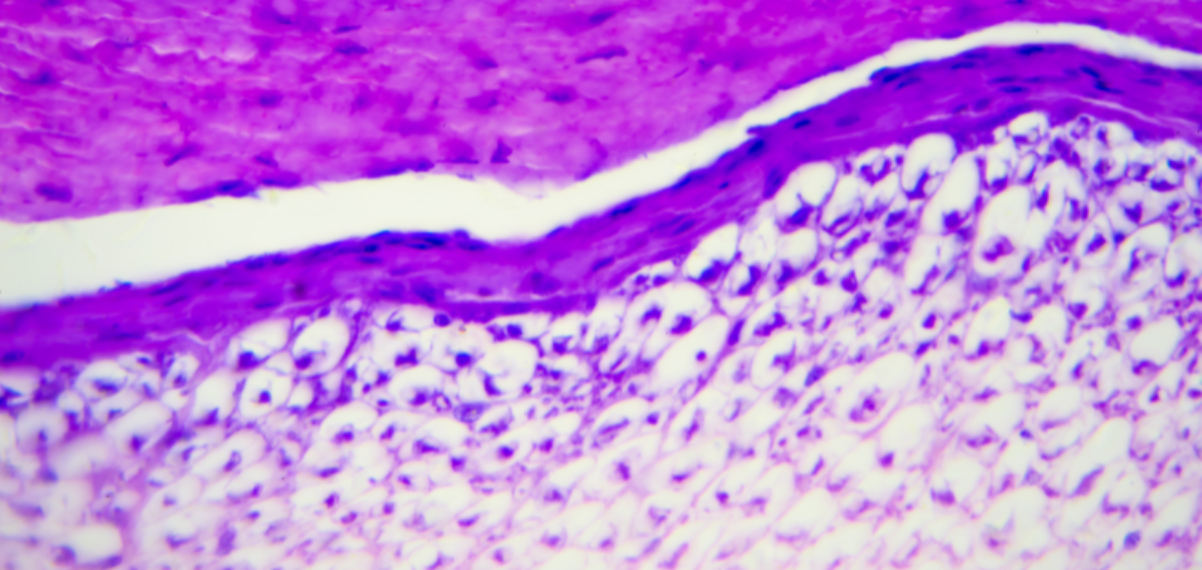

Fascia, ook wel connective tissue genoemd, is veel meer dan bindweefsel. Het vormt een complex en continu netwerk dat ons hele lichaam doorkruist en alles met elkaar verbindt. In de afgelopen jaren is steeds duidelijker geworden hoe belangrijk deze structuur is voor onder andere beweging, kracht, balans en ons immuunsysteem.

Fascia is grofweg onder te verdelen in twee typen:

• Tendineus connective tissue– zoals we dat kennen uit de anatomieboeken.

• Loose connective tissue, een dynamisch weefseltype dat werd ontdekt door Dr. Guimberteau en nog volop in de spotlight staat binnen wetenschappelijk onderzoek.